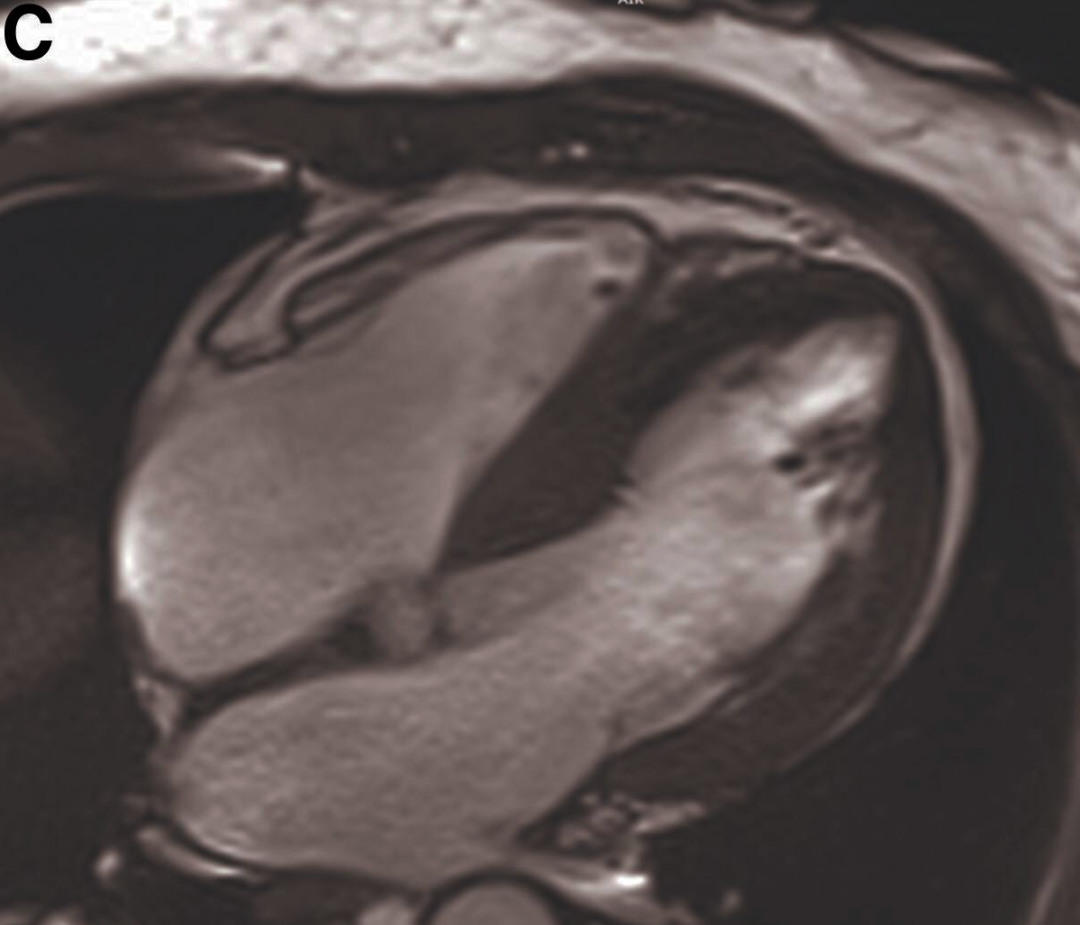

为进一步明确病变特征并排除其他潜在心肌疾病及晚期钆增强(LGE),行CMR检查,结果显示心尖部外侧壁小梁密集增厚(图 C,视频3)。呈结节状,且相互融合,看似“假性肿物”。

图C 心脏磁共振成像(心尖四腔心切面)显示左心室心尖段小梁呈簇状和结节状